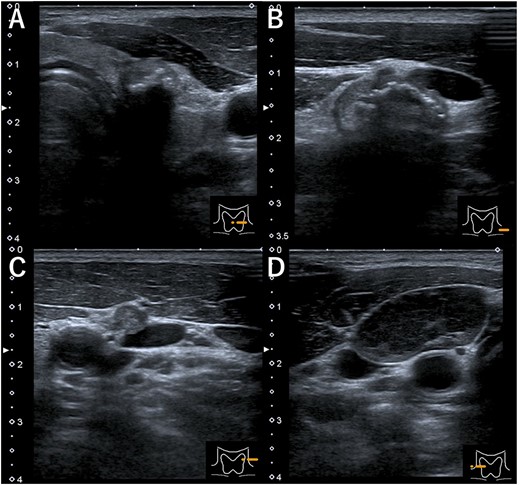

A 48-year-old man with a medical history of diabetes and pyorrhea alveolaris underwent computed tomography (CT). After the CT revealed a calcified mass in the left lobe of the thyroid and lymph nodes in the left cervical region, he was referred to our hospital. A solid mass was palpated in the left lobe of the thyroid and the left cervical lymph nodes. However, a soft mass was palpated in the right cervical region. He presented with no weight loss, no persistent fever and no night sweats (no B symptoms). Blood examination revealed that the patient was euthyroid, with a normal thyroglobulin level (17.4 ng/ml), a negative thyroglobulin antibody and a slightly high level of soluble interleukin-2 receptor (360 U/ml). Ultrasonography revealed a hypoechoic mass (18 × 14 mm) with microcalcification in the left lobe of the thyroid and a similar mass in the left cervical lymph node (#VI, 18 × 11 mm). The right cervical lymph node was enlarged (#Vb, 24 × 12 mm), although it was hypoechoic internally and had no microcalcification, differentiating it from the primary lesion (Fig. 1). CT revealed calcified nodules in the left lobe of the thyroid and the left cervical lymph nodes, but the right cervical lymph node mass was not calcified and showed no contrast effect (Fig. 2). Fine needle aspiration was conducted, and the mass in the left lobe of the thyroid was cytologically diagnosed as PTC. However, the right cervical lymph node mass remained class II. Thus, we preoperatively diagnosed PTC, cT1b N1b M0 cStage I and speculated that the right cervical lymph node mass expanded due to an unknown inflammation or malignant lymphoma. Total thyroidectomy, left modified neck dissection and biopsy of the right cervical lymph node were performed. The pathological diagnosis was PTC, 13 mm, T1b N1b (Fig. 3), with the right cervical lymph node diagnosed as NLPHL. Histologically, large tumor cells LP cells, termed “popcorn cells” were observed against a background of nodular or nodular diffuse proliferation of small lymphocytes. Immunostaining revealed that LP cells were CD3 (–), CD5 (–), CD10 (–), CD15 (–), CD20 (+), CD30 (–), CD79a (+), BCL6 (+) and EBER (–) in a background of B-cell-rich lymphoid follicles (Fig. 4). A postoperative fluorodeoxyglucose (FDG)-positron emission tomography (PET)/CT revealed no other accumulation except for the right cervical lymph node. The patient was diagnosed with Stage IA NLPHL, according to the Ann Arbor classification. Postoperatively, NLPHL treatment was prioritized, and external radiation (30.6 Gy) was applied to the right neck. PTC was considered a high-risk category for recurrence due to extranodal invasion of lymph node metastasis, and radioactive iodine therapy (ablative dose, 1110 MBq) was administered. Both PTC and NLPHL showed no recurrence 18 months after surgery.

Ultrasonography (A) hypoechoic mass (18 × 14 mm) with microcalcification in the left lobe of the thyroid, (B) mass in the left cervical lymph node (#VI, 18 × 11 mm), (C) mass in the left cervical lymph node (#Va, 5 × 5 mm) and (D) the right cervical enlarged lymph node (#Vb, 24 × 12 mm), hypoechoic internally with no microcalcification.